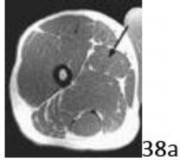

38a Figure 38a shows the cross-sectional anatomy of the proximal thigh. What structure is indicated by the arrow?

DISCUSSION: In Figure 38b, the arrow marks the adductor longus, which lies just deep to the superficial femoral artery. The adductor magnus is the larger, more posterior muscle on this

cross-sectional image. The adductor brevis is located between the adductor longus and magnus, deep to the deep femoral vessels. The sartorius is more superficial and covers the superficial femoral vessels. The gracilis is medial and more superficial. The Preferred Response # 38 is 2.